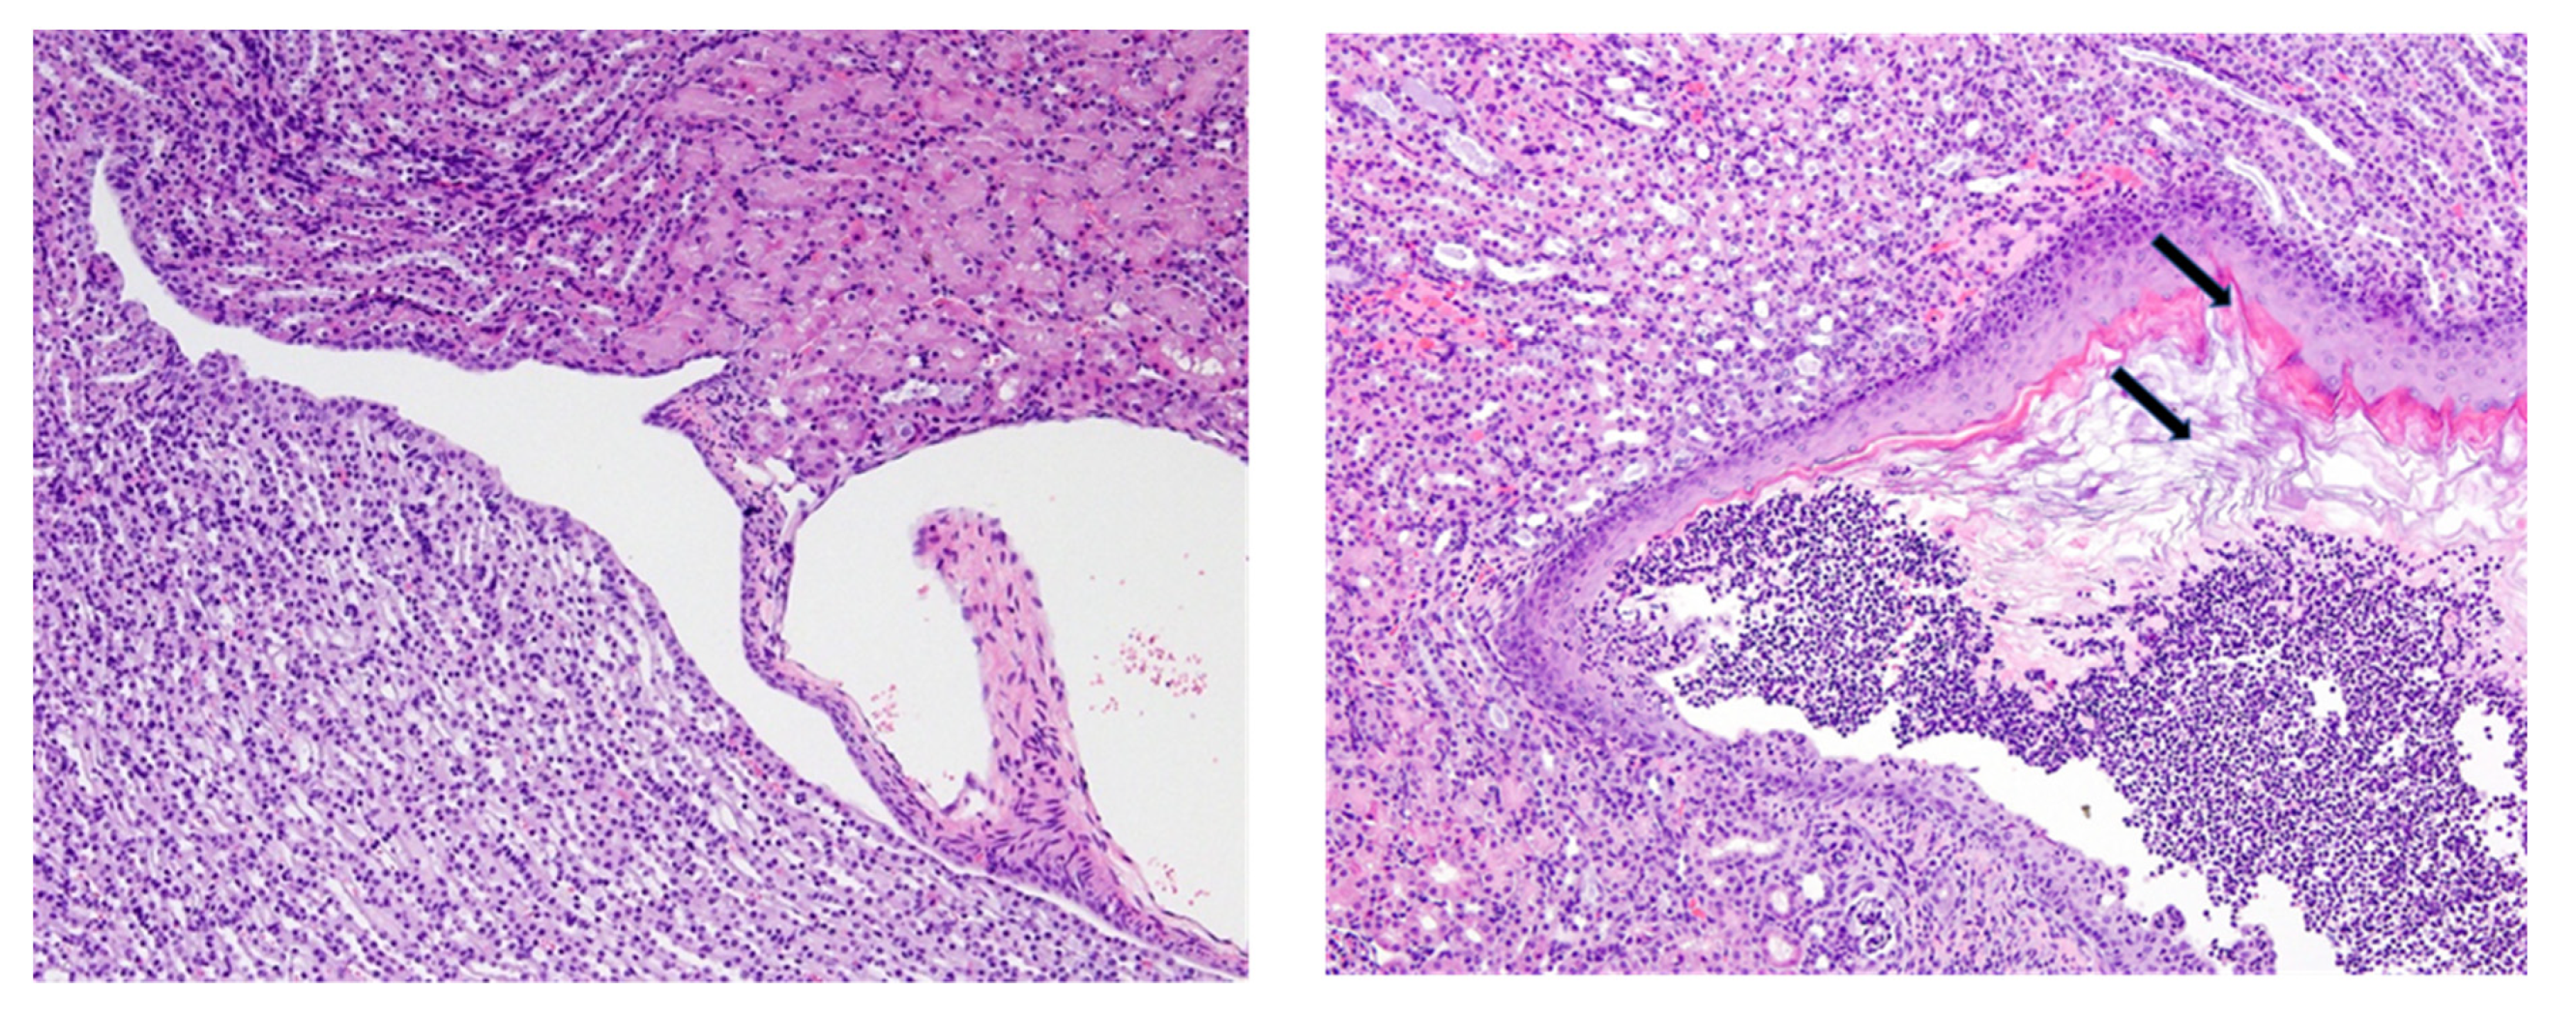

Disease was frequent regardless of injection (PBS, CFA, or CFA/DNA/PEP), suggesting that disease was a consequence of the diets and not the insults. In mice on the control diet, the urothelium lining of the renal pelvis and fornices consisted of a thin layer (1–3 cells thick) of polygonal cells with clearly defined nuclei (Figure 3, left image). In contrast, the urothelium in the VAD mice was a markedly thickened highly stratified squamous epithelium, with cornification of the upper layers and extensive sloughing of cornified cells into the lumen of the renal pelvis (Figure 3, right image). The urothelium in the VDD mice was normal, whereas the renal pelvis lesions in the VAD+VDD mice were indistinguishable from those of the VAD mice, being characterized by the accumulation of abundant desquamated keratinized squamous epithelium and cell debris in the lumen, with neutrophilic inflammation and bacteria.

Figure 3.

Histopathologic analyses of epithelial changes and inflammation in the renal pelvis and cortex of mice on vitamin A deficient (VAD) diets. Mice were injected with complete Freund’s adjuvant followed by incomplete Freund’s adjuvant approximately 3 weeks later and sacrificed approximately 3–4 weeks after the second injection. Representative tissue sections are shown (10× magnification). (Left) a mouse on the normal control diet. The urothelium lining the renal pelvis and fornices consisted of a thin layer (1–3 cells thick) of polygonal cells with clearly defined nuclei. (Right) in a VAD mouse, there was marked thickening of the squamous epithelium, with the cornification of upper layers (top arrow) and the extensive sloughing of cornified cells into the lumen of the renal pelvis (bottom arrow).

Lesions in the renal cortex were also limited to mice with VAD or VAD+VDD. In contrast to the normal arrangement of renal tubules and glomeruli in mice on normal diets and VDD mice, there was frequent, chronic inflammation and fibrosis extending into the adjacent medulla and cortex in both the VAD and VAD+VDD mice, with extensive scarring of the renal parenchyma in some cases. Overall, these renal lesions were indicative of an ascending pyelonephritis. Nephropathies and ascending bacterial UTIs were common in the VAD and VAD+VDD mice.